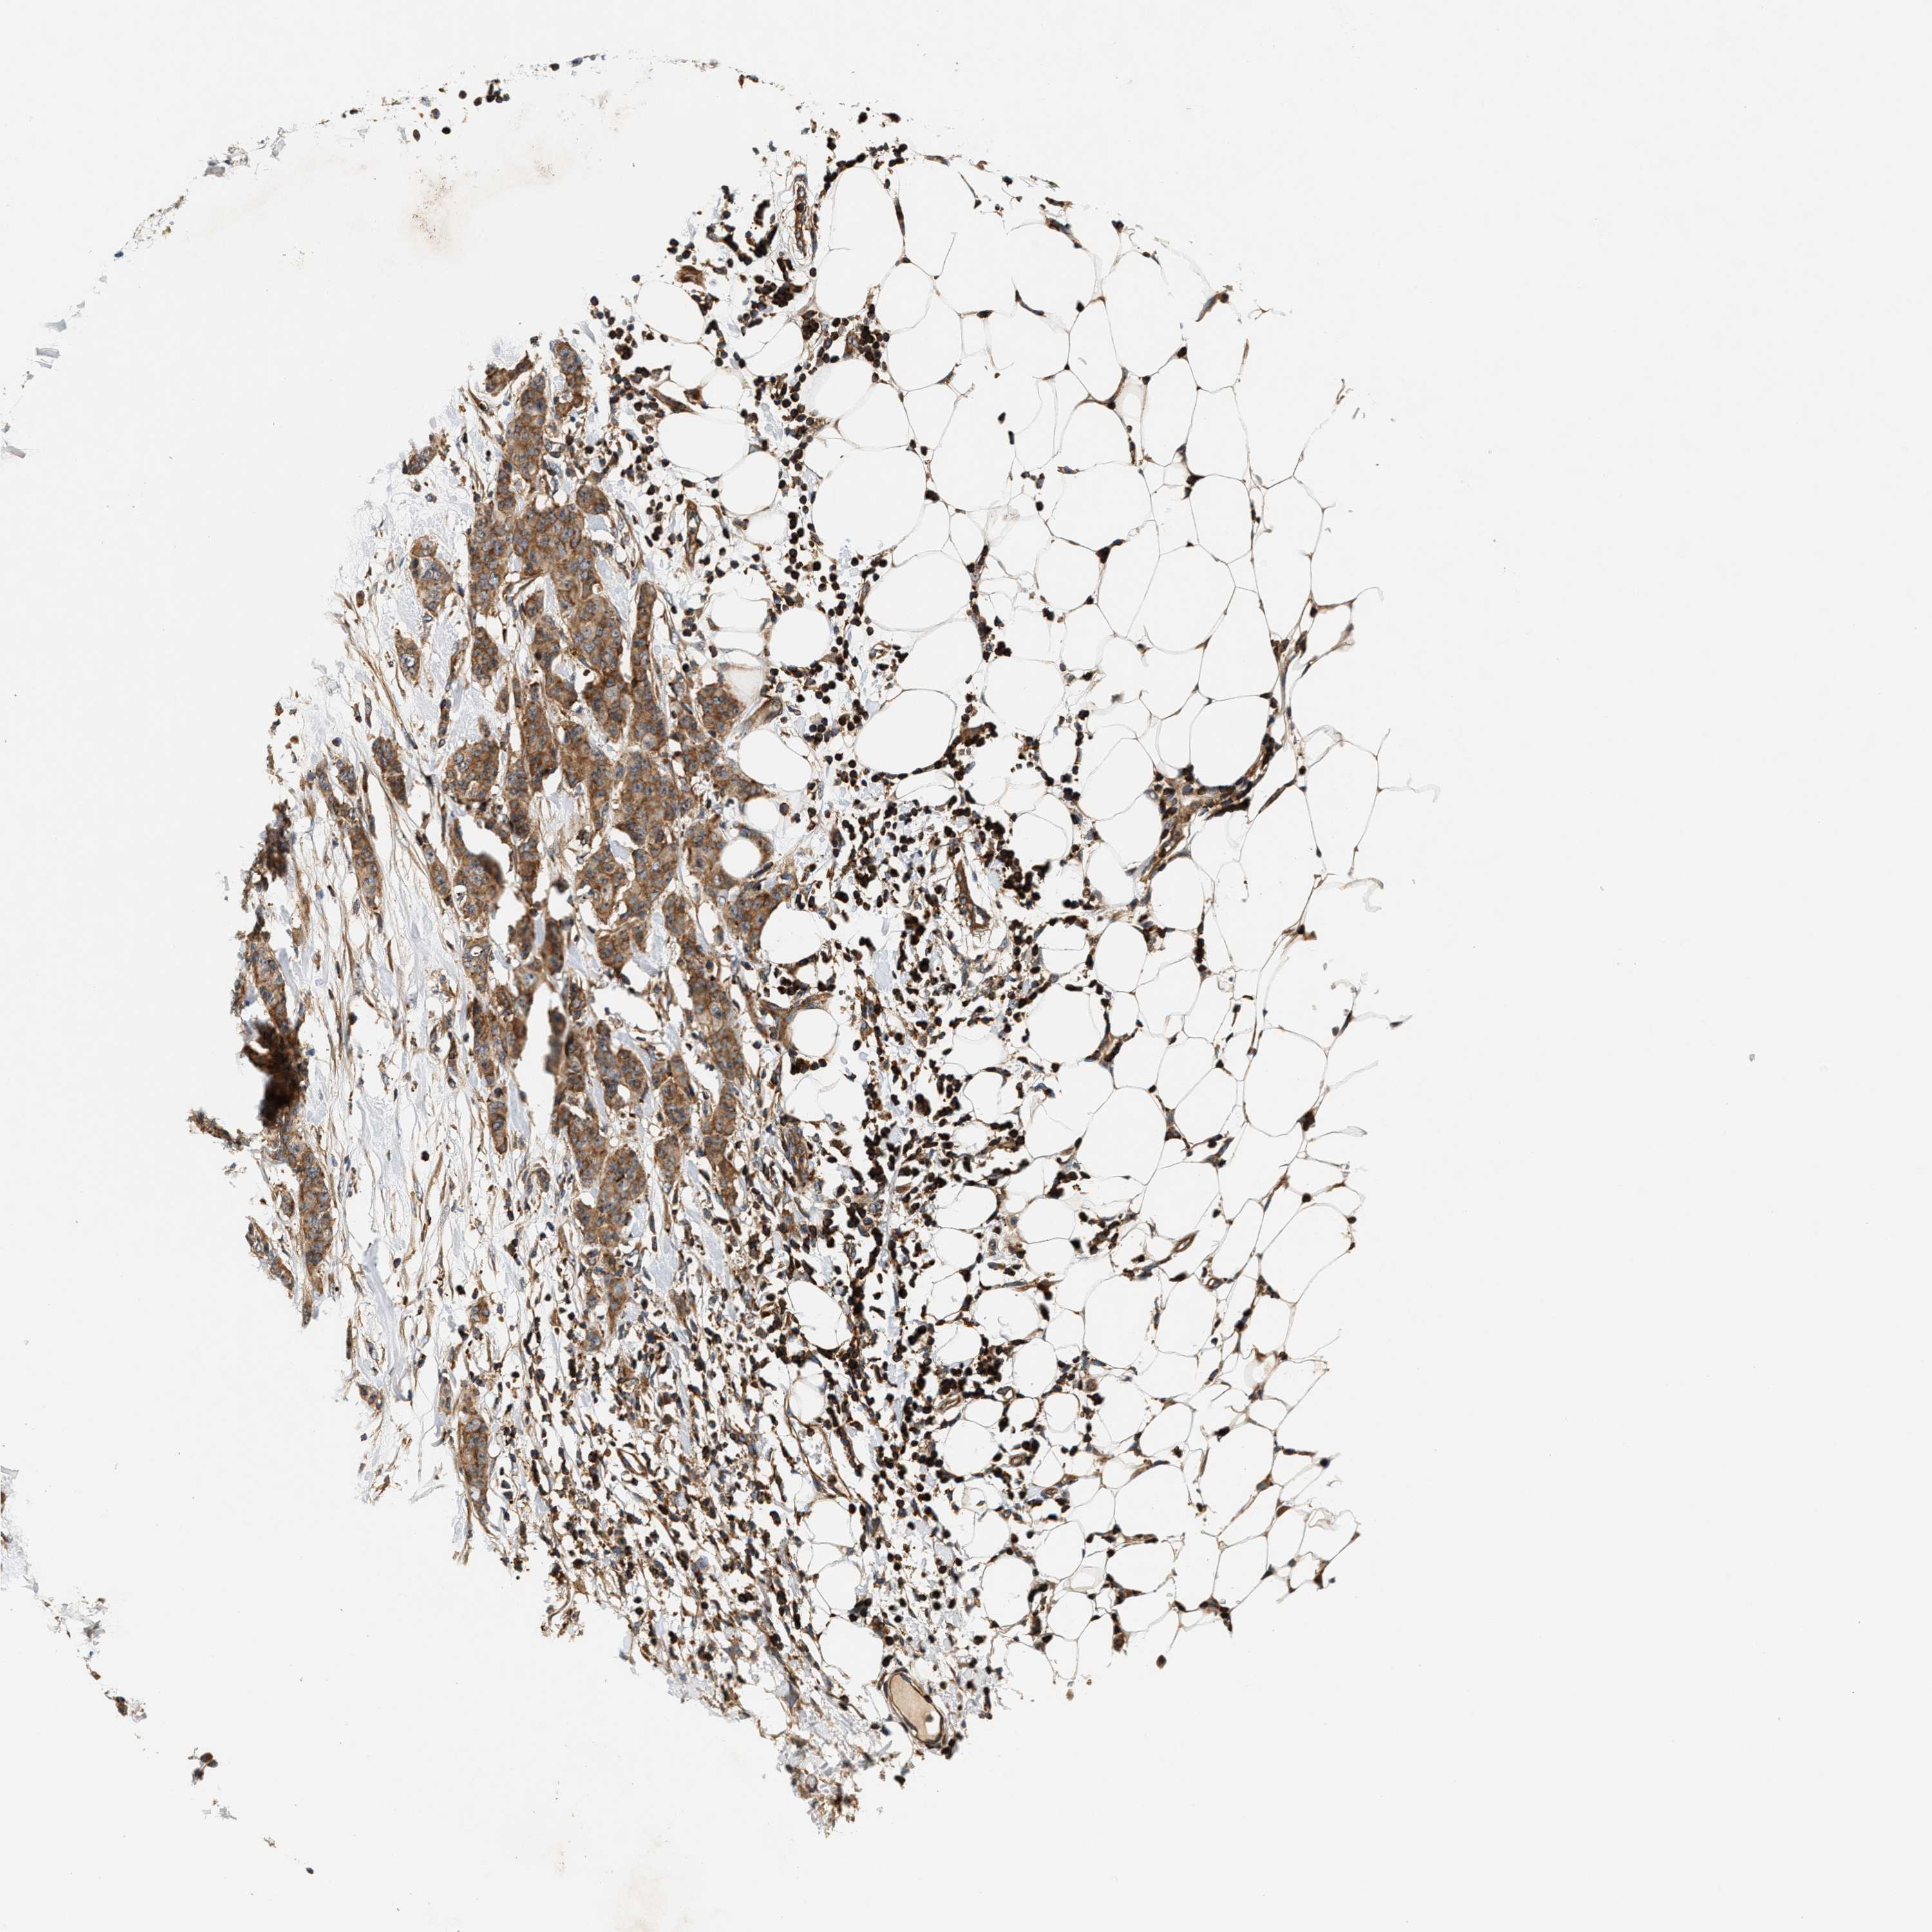

CANCER BREAST CANCER Show tissue menu

BRCA TCGA BRCA VALIDATION PROTEIN EXPRESSION

Breast cancer

Human cancer